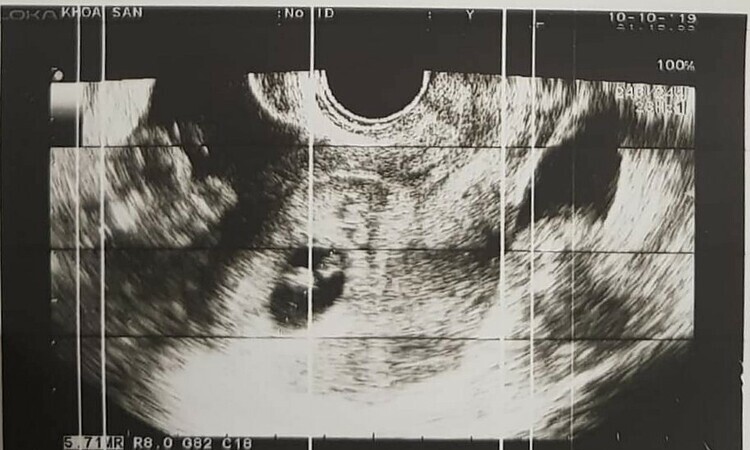

Kết quả siêu âm cho thấy có một thai nhi khoảng 7 tuần tuổi trong tử cung, thai cạnh buồng trứng trái. Bệnh nhân được chẩn đoán là song thai, vỡ ối và chảy máu trong tử cung và thai ngoài tử cung.

Đội ngũ bác sĩ phẫu thuật nội soi khẩn cấp, hút khoảng 500 ml máu trong buồng tử cung, cầm máu ngoài tử cung và thai nhi nằm lại tử cung. -Sau khi mổ, bệnh nhân được chăm sóc tiền sản tích cực. Em bé vẫn phát triển bình thường. Ảnh: Bác sĩ cung cấp